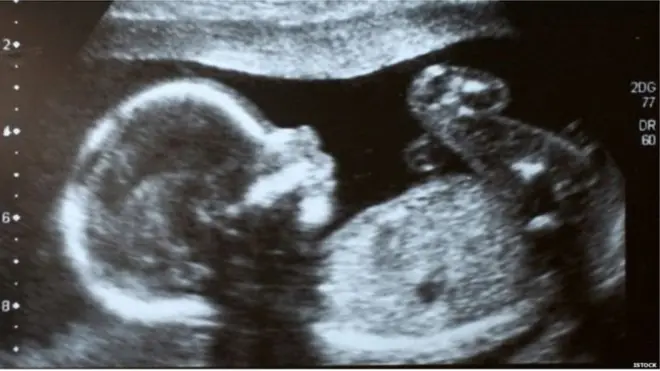

فی الحال پچھلے پانچ مہینوں سے میناکشی ہسپتال میں داخل ہیں۔ وہ 21 ہفتوں کی حاملہ ہیں۔ مئی 2017 میں ان کے بچہ دانی کی پیوندکاری ہوئی تھی۔ ان کی ماں نے انھیں اپنی بچہ دانی دی تھی۔

ایمبریو بنانے کے لیے ماں کے انڈوں اور باپ کے سپرم کا استعمال کیا جاتا ہے۔ میناکشی کے معاملے میں بھی ایسا ہی کیا گیا تھا۔ اس سال اپریل کے پہلے ہفتے میں لیب میں تیار کیے گئے ایمبریو کو ڈاکٹر شیلیش اور ان کی ٹیم نے ان کی بچہ دانی میں منتقل کیا تھا۔